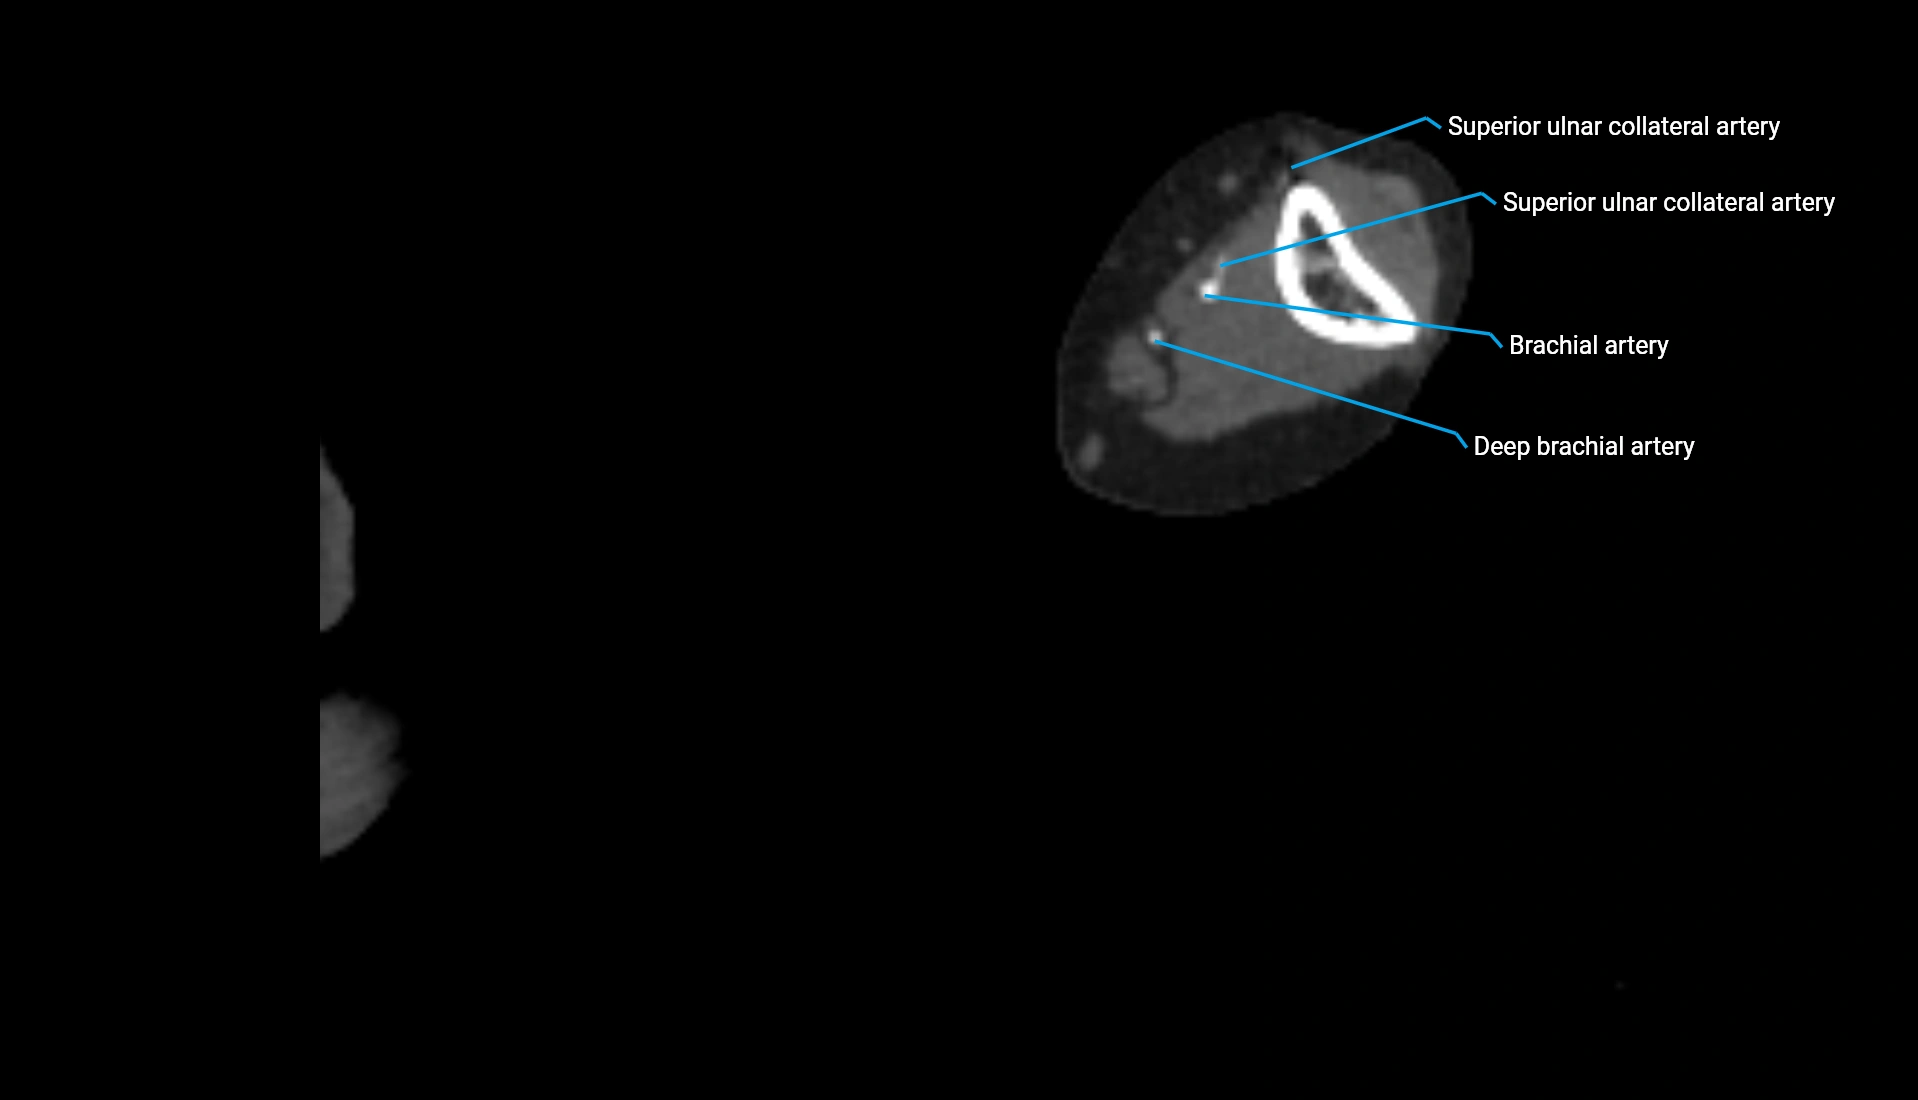

CT Appearance

Non-Contrast CT:

• Cortex: High-density, sharply defined

• Subchondral bone: Dense cancellous matrix

• Articular surface: Smooth concave contour articulating with the capitellum

• Excellent for evaluating bone integrity, alignment, and subtle fractures